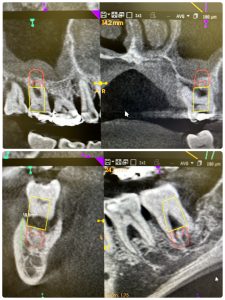

➀

4ヶ月で治る、年齢20代foreigner

右下はインプラントがベスト

私がやれば、悪くなりませんよ!🤪